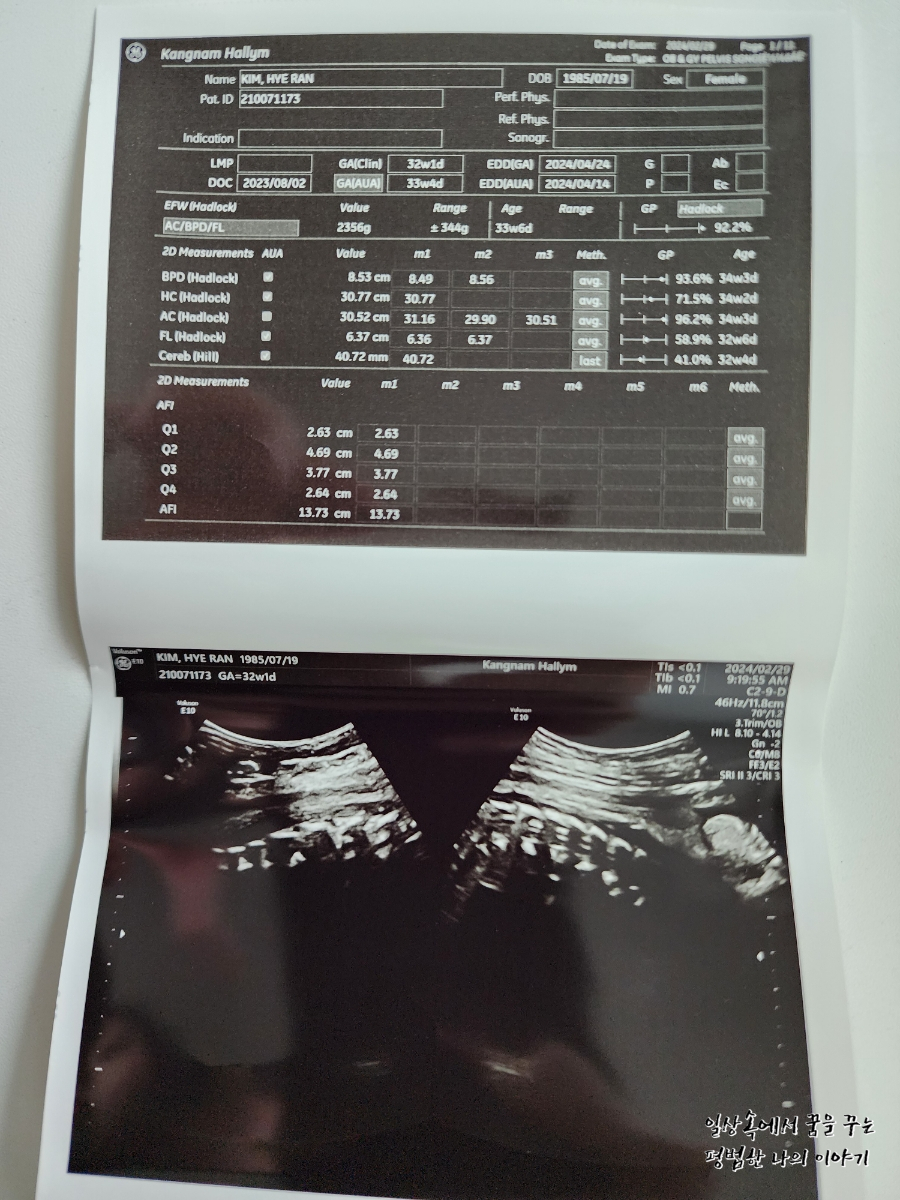

FHR(Fetal Heart Rate, 심장박동 수): 149bpm

3주 만에 방문한 병원에서 우리 딸내미는 무척이나 커져있었는데 지난번 정기검진에서는 길이랑 배 둘레만 원래 주차 수에 비해 컸다면 이번 정기검진에서는 전체적으로 2주 이상 커져있었다. 의사 선생님이 지금 주차 수에서는 알기 어렵고 막달이 돼봐야 알 것 같기만 왠지 4킬로는 훌쩍 넘을 것 같다고 하셔서 걱정이다. 무엇보다 배 둘레랑 머리둘레가 큰 편이라 분만의 어려움이 예상된다고 하시더라. 그래도 자연분만에 대한 생각은 아직까지 변함없긴 하지만 아직 시간이 많이 남았으므로 좀 더 지켜보기로... 그리고 이번 정기검진에서는 백일해 주사를 맞았다. 임산부는 태아를 위해서 첫째 때맞았더라도 추가로 맞아야 하고 남편과 친정엄마는 이미 첫째 때맞으셨기 때문에 추가로 다시 맞지 않아도 된다.